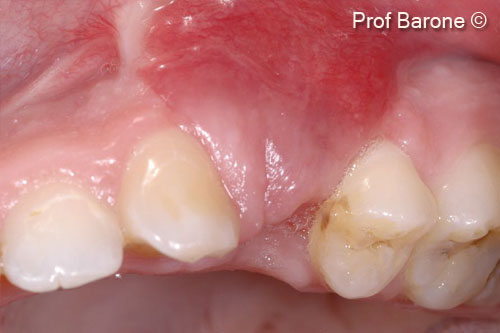

Tình hình ban đầu

Một bệnh nhân nữ (27 tuổi) có biểu hiện nhiễm trùng cấp tính và mủ từ lỗ rò ở miệng.